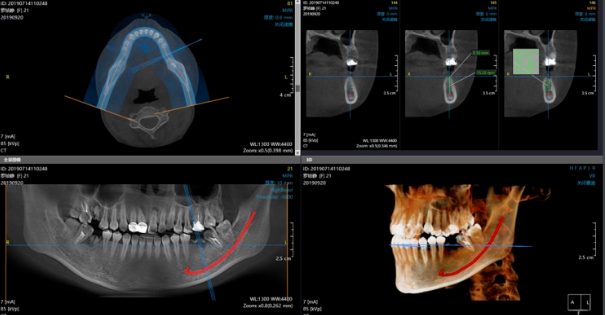

喺種植牙手術之前,術前檢查系必不可少嘅。其中,CT掃描係一種常用嘅影像檢查方式。通過CT掃描,醫生可以獲得患者口腔內部嘅三維結構信息,包括骨質密度、牙齒位置和周圍組織情況等。呢對於確定種植牙手術嘅可行性和制定個體化嘅治療方案非常重要。

種植牙手術後嘅3-6個月,通常需要進行第三次CT掃描。呢段時間係讓種植體同患者嘅頜骨融合,形成穩定嘅支持基礎嘅關鍵時期。通過CT掃描,醫生可以准確評估融合嘅程度,並決定下一步嘅修復方案。